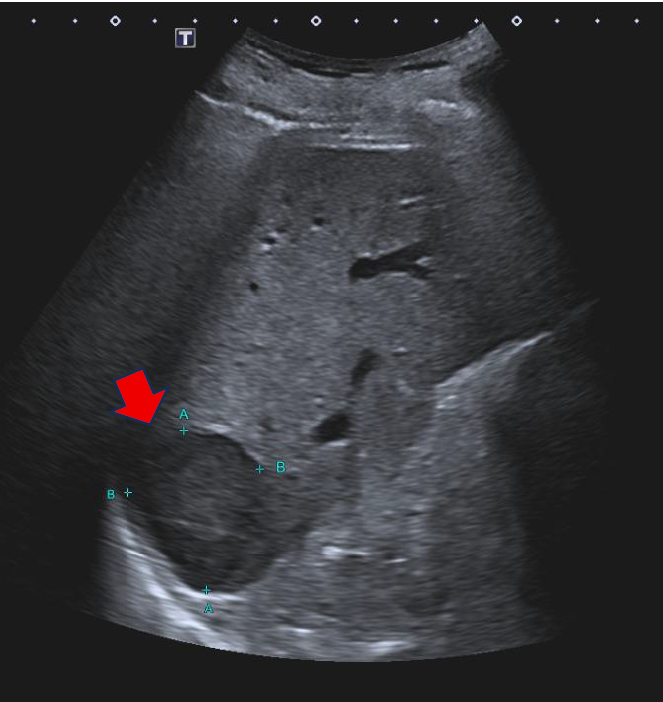

Caso 04

Maria Alcaraz Hernandez